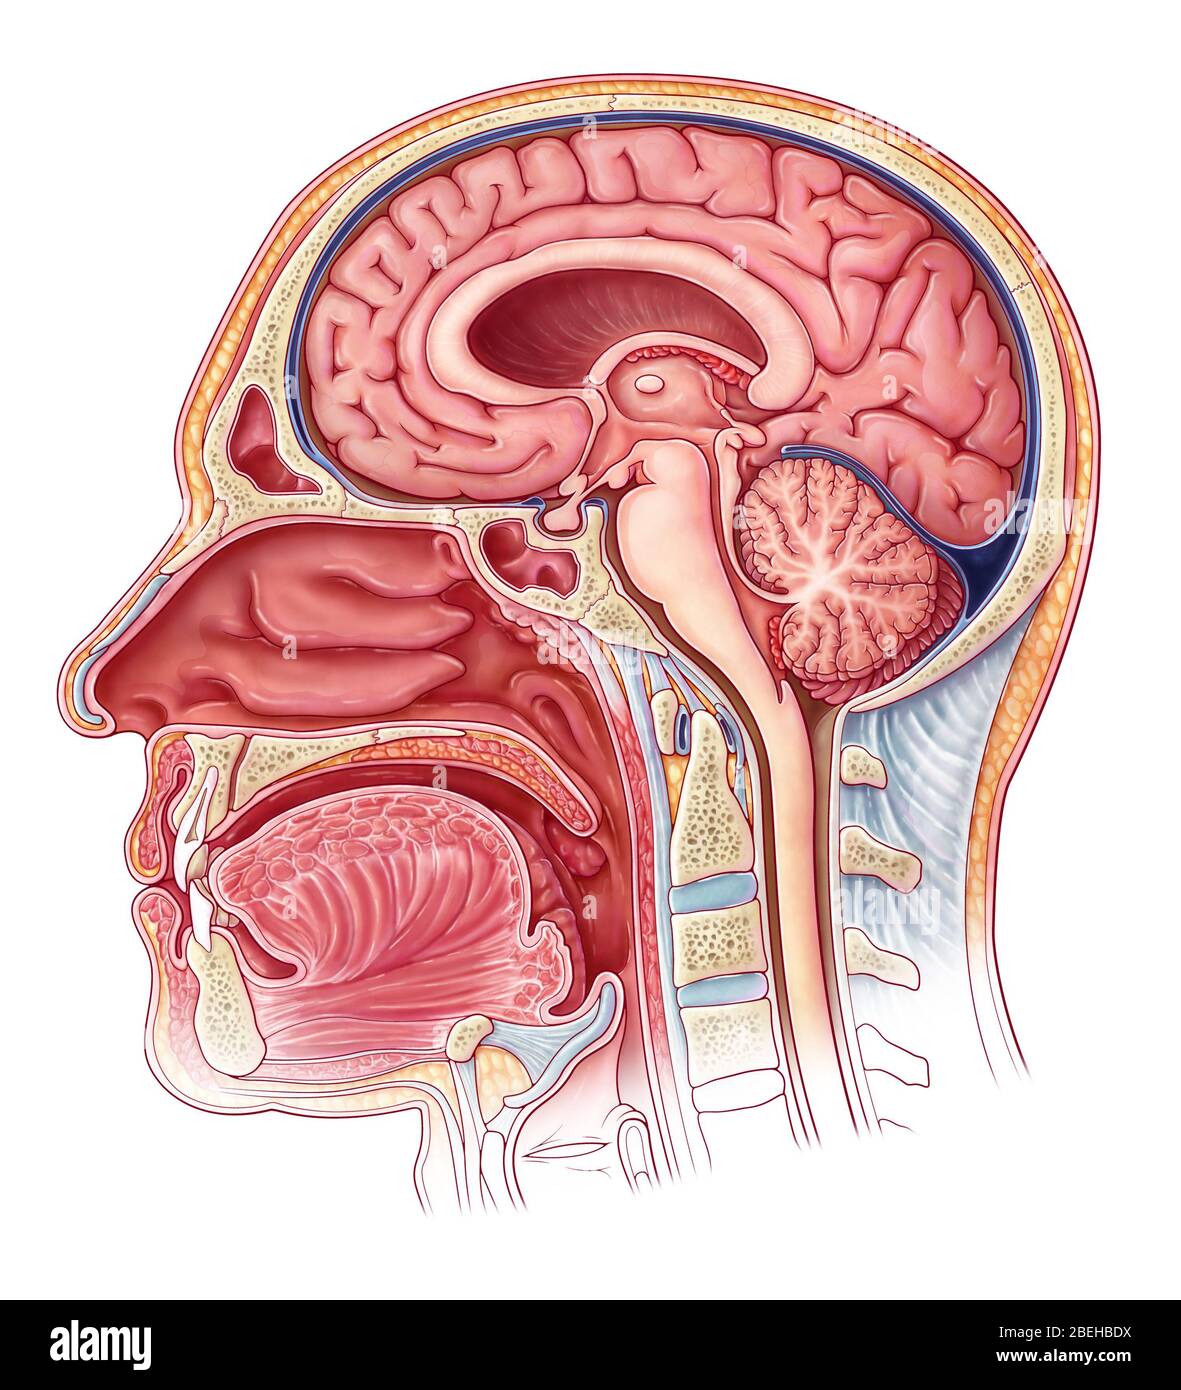

RMG155NT–Illustration einer sagittalen Abschnitt der dritten und vierten Ventrikel des Gehirns. Die Ventrikel enthalten Liquor cerebrospinalis, die das Gehirn dämpft. Dies ist eine historische Darstellung aus den 1890er Jahren.

RMG155NW–Verbesserte Darstellung der sagittalen Abschnitt der dritten und vierten Ventrikel des Gehirns Farbe. Die Ventrikel enthalten Liquor cerebrospinalis, die das Gehirn dämpft. Dies ist eine historische Darstellung aus den 1890er Jahren. (Abb. BS4911)